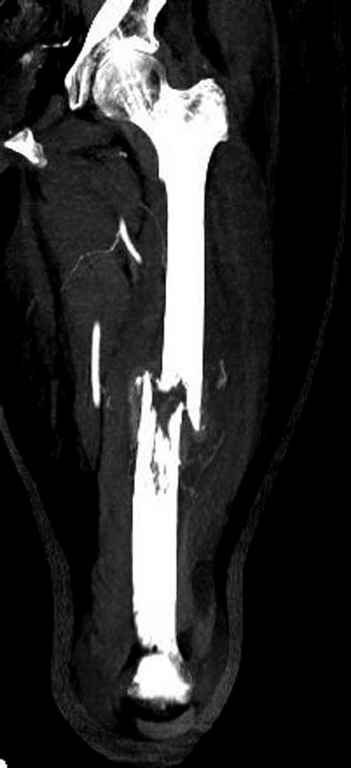

Известно, что многие из нас независимо от метода лечения и стадии первичной опухоли проводят интрамедуллярное штифтование при различных патологических состояниях бедра, включая патологические переломы.

Со слов, больная ничем не болела, только последние 3 месяцев чувствовала боли в бедренной области. КТ брюшной полости подтвердил увеличенную правую почку. (5-6)

Для предупреждения кровотечения во время рассверливания, за день до операции провели эмболизацию сосудов питающий метастаз. http://radiology.rsnajnls.org/cgi/reprint/150/3/673.pdf (7-11, 12-15-16)

С минимальным рассверливанием и ретроградным методом провели остеосинтез бедра 12 мм гвоздем. (17-20)

Кровопотеря во время операции меньше 100 мл.